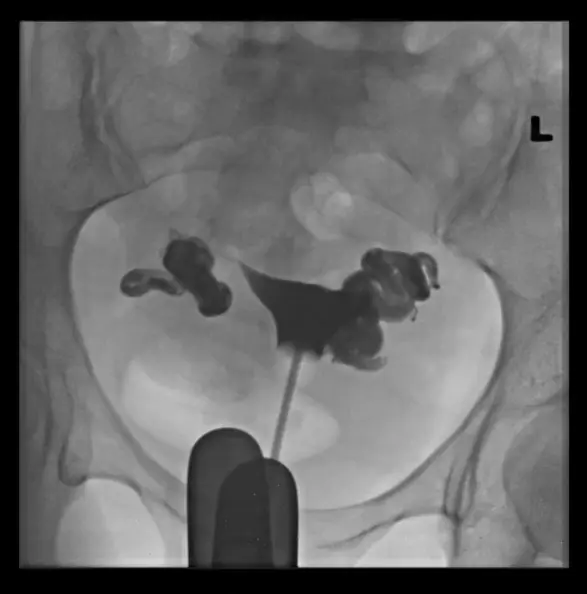

這是一張骨盆腔的子宮輸卵管攝影(HSG)正面觀影像,使用了顯影劑(contrast medium)進行檢查。

- 子宮(Uterus):影像中央可見顯影劑填充的子宮腔,呈現倒三角形,邊緣平滑,無明顯的充盈缺損(filling defect),顯示子宮腔形態大致正常。

- 顯影劑成功進入兩側輸卵管。

- 關鍵發現:兩側輸卵管的遠端(distal end,即壺腹部與繖部區域)呈現明顯的**囊狀擴張(cystic dilation)**與腫大,形狀類似香腸或燒瓶(retort-shaped)。

- 腹腔溢流(Peritoneal spill):正常情況下,顯影劑應從輸卵管末端溢出並散佈在腹腔內。但在此影像中,完全未見顯影劑溢流至腹腔(no free spill),顯影劑被侷限在擴張的輸卵管末端內。

- 綜合判斷:雙側輸卵管遠端阻塞併擴張,且無顯影劑溢出,為典型的**輸卵管積水(Hydrosalpinx)**影像特徵。

病人為年輕女性,主訴不孕。HSG 影像顯示雙側輸卵管遠端明顯擴張、腫大且顯影劑無法流出至腹腔,此為**雙側輸卵管積水(Hydrosalpinx)**的典型表現。積水內的液體具有胚胎毒性,會影響試管嬰兒(IVF)的著床率,因此是正確診斷。